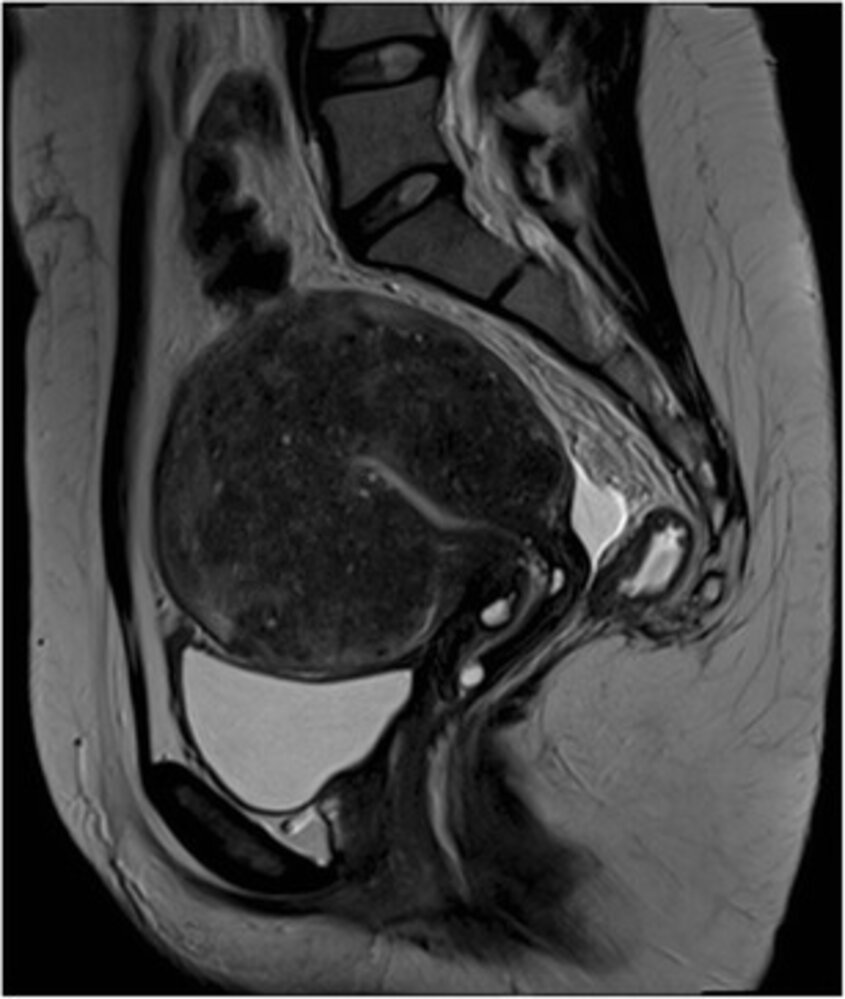

• Obtain MRI pelvis with and without IV contrast if: [2][5][6]

• TVUS results are inconclusive

• The uterus cannot be completely visualized with TVUS

• Surgery is planned